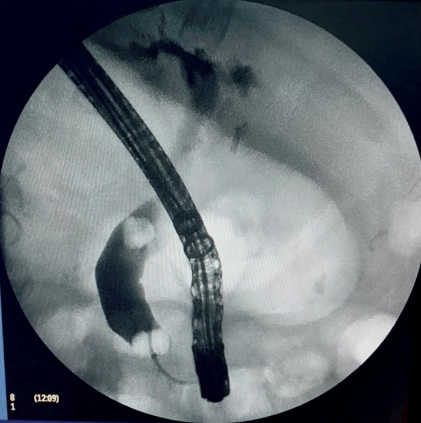

ERCP was performed successfully over 0.035-inch diameter guidewire, a Haraldsson type 3 duodenal papilla;3 Cholangiography showed a fill defect of 8mm, with a no bleeding, complete sphincterotomy, the common bile duct stone was extracted with balloon, without complication. Patient was followed for 6hours, and previous discharge, pain appeared at right upper quadrant. Colicky pain, diaphoresis, nausea and vomiting. We made new laboratory test, showing, and a drop of hemoglobine from 15g/dl previously to 10g/dl creating us the idea about patient was bleeding, maybe from the sphincterotomy, just giving no surgical management until then. Urgent computed tomography (CT) scan exhibited 13x11 cm subcapsular hepatic hematoma on the surface of the right hepatic lobe (Figures 1-4). He was treated with conservatory management with Tomographic control every 10days in 2 episodes, and every 2months, with hematoma regression until the month 6th.

Figure 2 First CT with right lobe hematoma.